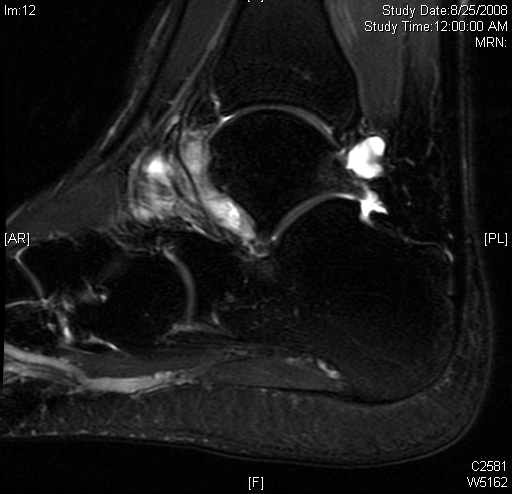

Shows multiloculated, heterogeneous mass.

“Triple Signal Intensity sign”; hypointense, isointense and hyperintense with fat on T2 – weighted MRI imaging. This sign is present in 30 to 50% of the cases. (Fig.3)

Under contrast enhancement Synovial Sarcoma appears heterogeneous and demonstrate areas of nodular enhancement.

In approximately 30% of cases a multiple vascular cannel may be identified

Synovial sarcomas may have a cystic appearance and are often mistaken for ganglion cysts especially those adjacent to tendons and in the foot and ankle.